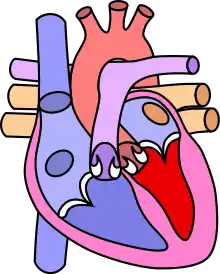

![]() | |

| Diagram of a healthy heart and one with tetralogy of Fallot | |

Tetralogy of Fallot (TOF), formerly known as Steno-Fallot tetralogy,[9] is a congenital heart defect characterized by four specific cardiac defects.[4] Classically, the four defects are:[4]

- pulmonary stenosis, which is narrowing of the exit from the right ventricle;

- a ventricular septal defect, which is a hole allowing blood to flow between the two ventricles;

- right ventricular hypertrophy, which is thickening of the right ventricular muscle; and

- an overriding aorta, which is where the aorta expands to allow blood from both ventricles to enter.

Four malformations

"Tetralogy" denotes four parts, here implying the syndrome's four anatomic defects.[2] This is not to be confused with the similarly named teratology, a field of medicine concerned with abnormal development and congenital malformations (including tetralogy of Fallot). Below are the four heart malformations that present together in tetralogy of Fallot:

| Right ventricular hypertrophy | The right ventricle is more muscular than normal, causing a characteristic boot-shaped (coeur-en-sabot) appearance as seen by chest X-ray. Due to the misarrangement of the external ventricular septum, the right ventricular wall increases in size to deal with the increased obstruction to the right outflow tract. This feature is now generally agreed to be a secondary anomaly, as the level of hypertrophy tends to increase with age.[44] |